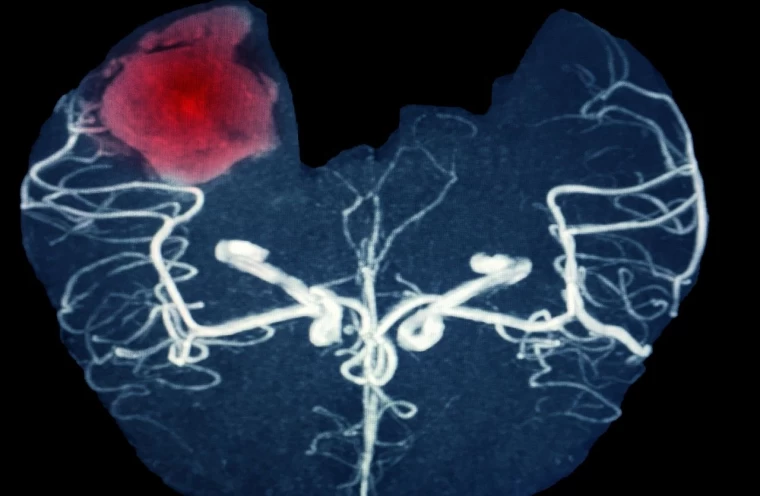

Beyin kanaması, aniden gelişen ciddi bir tıbbi durumdur ve beynin içerisindeki kan damarlarının patlaması sonucu meydana gelir. Bu durum, beynin normal fonksiyonlarını bozan bir basınca yol açar. Genellikle bir travma veya yüksek tansiyon gibi sebeplerden kaynaklanan beyin kanaması, anında müdahale gerektiren ve ölümcül sonuçlar doğurabilecek bir durumdur. Beyin kanamasının belirtilerini ve nasıl anlaşılabileceğini anlamak, erken müdahale şansını artırır. Bu yazıda, beyin kanaması belirtileri ve bu durumun risk faktörleri hakkında detaylı bilgi vereceğiz.

Beyin kanaması, çeşitli faktörler tarafından tetiklenebilir. En yaygın nedenlerden biri yüksek tansiyondur. Yüksek tansiyon, beyin damarlarına fazla baskı yaparak bu damarların zayıflamasına ve patlamasına yol açabilir. Aynı zamanda, kafa travmaları, damar anormallikleri, tümörler ve bazı enfeksiyonlar da beyin kanamasına yol açabilir. Kan sulandırıcı ilaçların aşırı kullanımı da kanama riskini artırır. Ayrıca, genetik yatkınlık ve yaşlanma, damarların zayıflamasına neden olarak beyin kanamasını tetikleyen diğer önemli faktörlerdir.

Yüksek tansiyon, beyin kanaması için en önemli risk faktörlerinden biridir. Özellikle kan basıncının çok yüksek olduğu durumlarda, beyin damarları üzerinde aşırı bir baskı oluşur ve bu da damarların patlamasına neden olabilir. Kan basıncının 180/120 mmHg seviyesinin üzerine çıktığı durumlarda, beyin kanaması riski önemli ölçüde artar. Bu tür yüksek tansiyon vakalarında, kişilerin derhal tıbbi yardım alması ve tansiyonlarını kontrol altına alacak tedavi yöntemlerini uygulaması gerekmektedir.